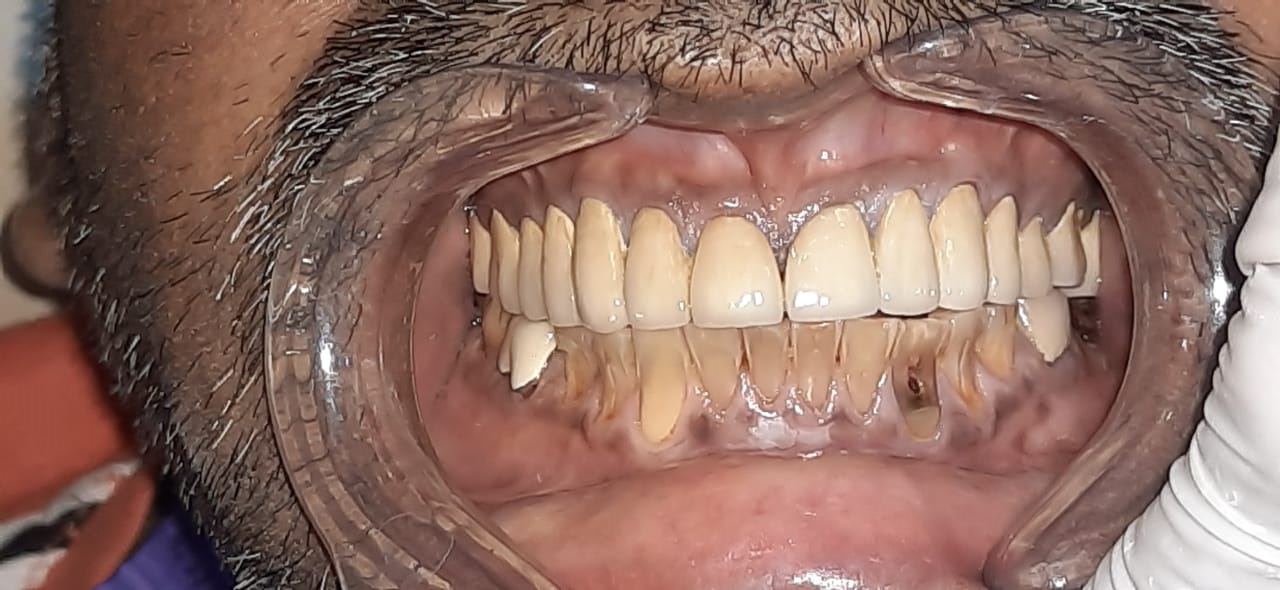

Patient wanted to get a new set of new teeth as old teeth were severely attrited and he was not able to chew. Medical history was taken and patient was fit for all the dental procedure. A detailed radiographic examination was conducted with the help of opg Treatment planning. A detailed case history along with radiological investigation and recording of of Bite of patient it was done in first visit. An appliance to relieve occlusion was given for 21 days Root canal treatment it was perform for all the teeth in subsequent visits. Occlusion was recorded using a specialised semi adjustable articulator. A temporary prosthesis was given to be used for or 15 days. A permanent Restoration was fabricated using pfm Crowns. A patience on patient end is a much needed thing as it involves time duration of of 1 to 2 months. Patient has to be absolutely serious about the treatment protocols which we are following as it involves use of appliances on patients end. Patient has to leave habit of eating Supari and tobacco as it was the cause in in severe reservation and attrition of teeth the artificial prosthesis is a finely crafted instrument that needs to be used with precision. so patients willingness and a positive mindset is Paramount in treating such cases.

Exciting News! Discover the Steps of Full Mouth Rehabilitation for a Dazzling Smile! Are parafunctional habits like kharra and ghutka taking a toll on your dentition? Say goodbye to improper chewing, loss of facial aesthetics, and digestive troubles with our expert team at Chintamani Dental Clinic!

Step 2: State-of-the-Art Treatments Experience top-notch root canal treatments and effective temporization protocols for optimal oral health.

Step 4: Exceptional Dental Lab Our second nature Dental lab crafts your dream smile with utmost precision.